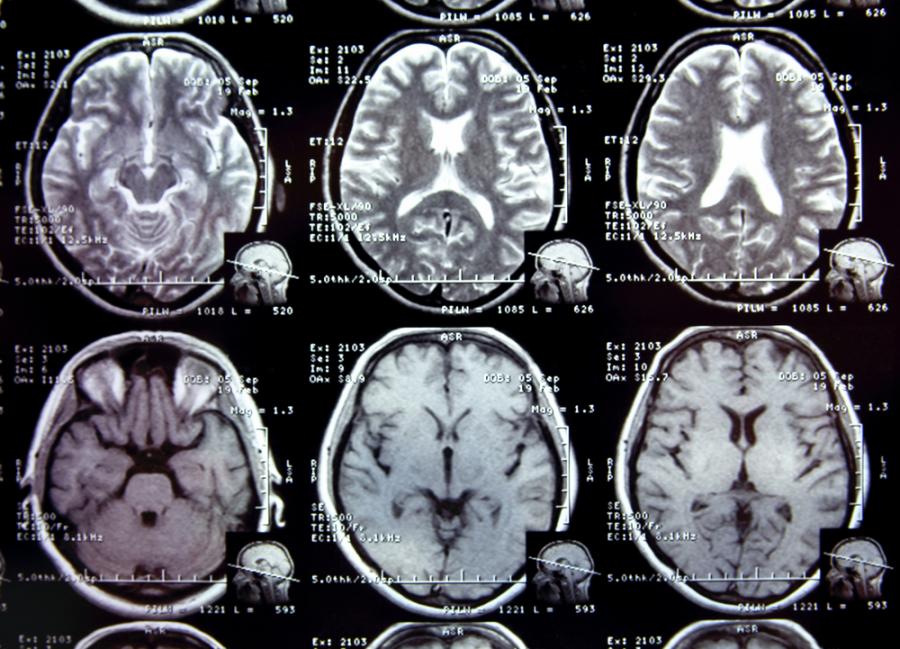

Рекик и екипът ѝ са използвали голямо количество данни от триизмерни изображения на мозъка, като например изображения, получени чрез ядрено-магнитен резонанс, и са съставили от тях двуизмерни карти, на които са представени невронните мрежи в мозъка. Всяка мрежа, известна като „конектом“ и подобна на електрическа схема, разкрива приличаща на лабиринт система от неврони, свързващи различните зони на мозъка.

На базата на тези конектоми изследователите са създали шаблони на връзките в мозъка, които служат като невронни отпечатъци. Шаблоните картографират как е структуриран мозъкът, когато всички невронни мрежи са правилно подредени и функционират както трябва (като се вземат предвид естествените вариации, очаквани при дадена популация от здрави хора).

„Мозък, в който е възникнало разстройство, ще изглежда като карта с невронни мрежи, различаващи се от наблюдаваните в шаблона на здравия мозък“, обяснява Рекик, директор на Лабораторията за изследване и анализ на мозъка и сигналите (BASIRA) към Техническия университет в Истанбул, Турция. „Когато поставите такава карта върху шаблона, дисфункцията се откроява.“